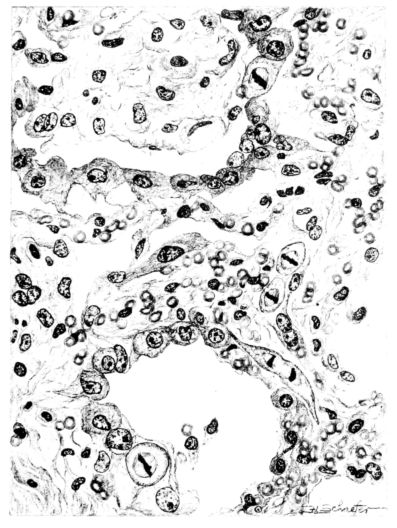

FIG. III. AUTOPSY NO. 90. DRAWING FROM A LESION OF THE TRACHEA (SOMEWHAT OLDER THAN THAT ILLUSTRATED IN FIGURE II). THE MUCOSA IS ENTIRELY LACKING. CONGESTION AND EDEMA ARE THE STRIKING FEATURES IN THE SUBMUCOSA. THE NECROTIZING PROCESS HAS EXTENDED INTO THE MUCUS GLANDS. THIS IS SHOWN IN THE LOWER PICTURE.

The changes are less marked, perhaps, in the trachea than in its finer ramifications. The mucosa is constantly more or less destroyed and large areas, usually focal, are entirely devoid of their epithelial covering. This is replaced by a sparse exudate, composed largely of red blood cells, mucus, a small amount of fibrin, and nuclear fragments (Fig. II). It may dip into the submucosa for a short distance, but usually these indentures are associated with the ducts of the mucous glands into which the inflammatory reaction extends. A more striking feature than the exudate, however, is the edema and the congestion of the submucosa. The loose areolar tissue of the submucosa is spread widely apart, and throughout it distended blood vessels are very conspicuous. Occasionally such a vessel is broken and actual hemorrhage appears in the submucosa. Occasionally, too, the inflammation extends down the duct to the mucous gland itself, and here, also, aplastic inflammatory reaction is evident, inasmuch as the acini now stain intensely red with the cells undifferentiated from each other and specked here and there by broken remains of the dead nuclei (Fig. III). After the disease has continued for a short period, even at the end of five or six days, some regeneration of the epithelial lining may be seen (3) (Fig. IV). But despite this, the acute picture persists, and there goes on, side by side, an attempted repair characterized by epithelial regeneration and the same evidence of acute change. Since the lesion is essentially a superficial one, scars or contractures of any extent are not encountered in the trachea, even in examples of the disease that have ended fatally only after many weeks.[4]